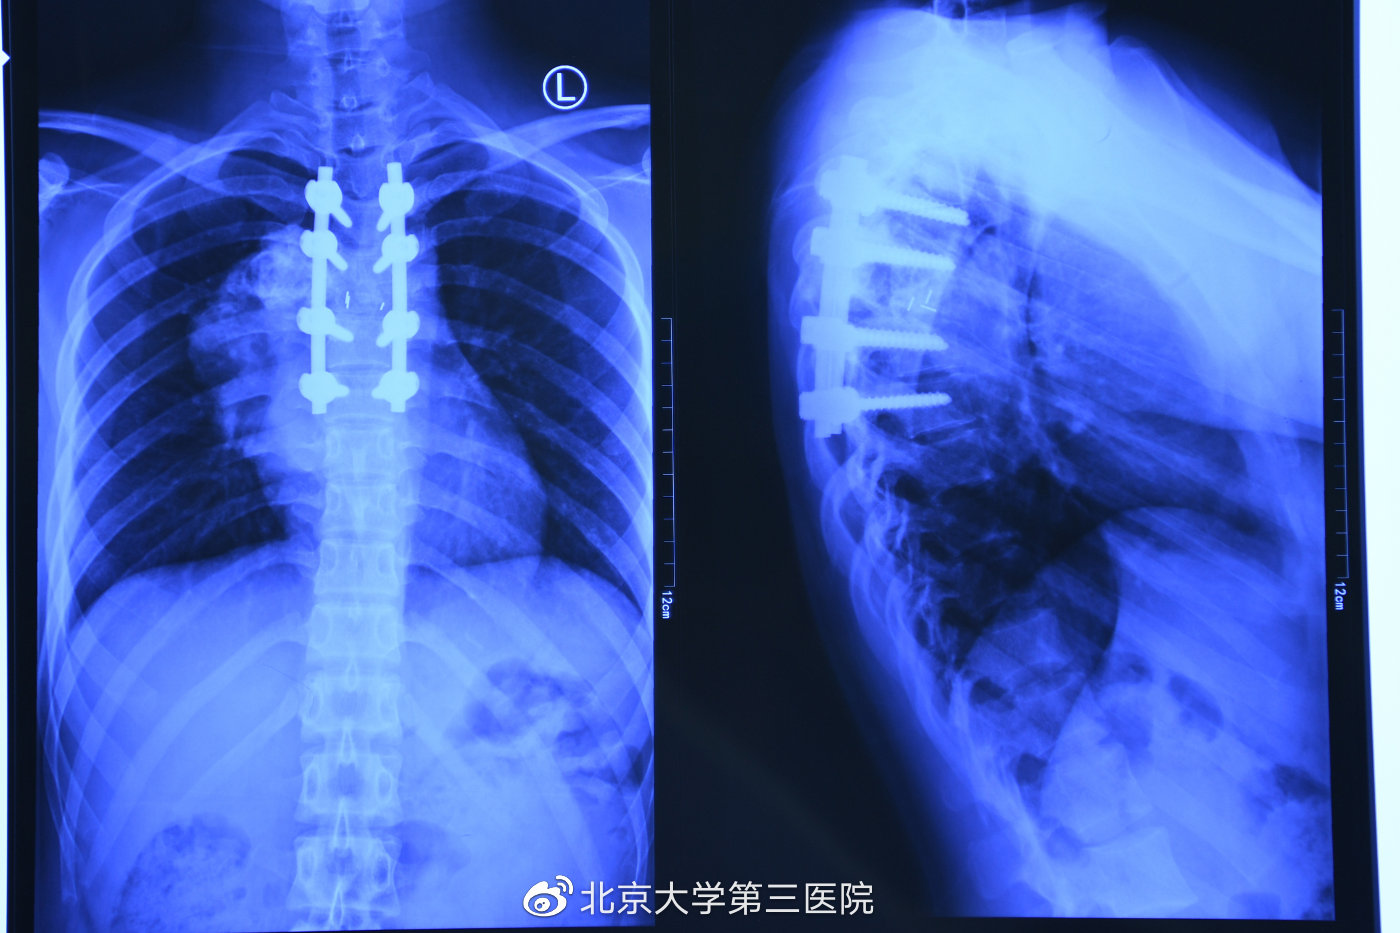

25岁的小文,被巨大的胸椎骨巨细胞瘤折磨着,肿瘤越长越大,吞噬了她的三节胸椎。1月9日,北医三院刘忠军教授团队在手术台上奋战了3个多小时,将小文被肿瘤“吃掉”的三节胸椎彻底“拿掉”,植入了为她量身定制的3D打印胸椎。这台手术对于小文来说,是避免她将来截瘫的唯一选择。记者了解到,这台手术也是今年1月1日施行《定制式医疗器械监督管理规定(试行)》后,完成的第一台定制式医疗器械植入手术。

此前,我国已经展开了3D打印钛合金内植物临床试验,并顺利进行了多台手术,这让很多疑难疾病的治疗获得突破性进展。刘忠军说,现在我国3D打印的“私人定制”植入物技术在国际上处于领先地位。小文这次手术要用到三节胸椎,术前医生为小文进行了CT检查,相关数据传输给3D打印工程师之后,技术人员将影像片的数据转化为定制关节立体成像所需要的数据,设计出数字模型,72小时内即完成加工,而在欧美,这样的胸椎加工需要3个月才能完成。